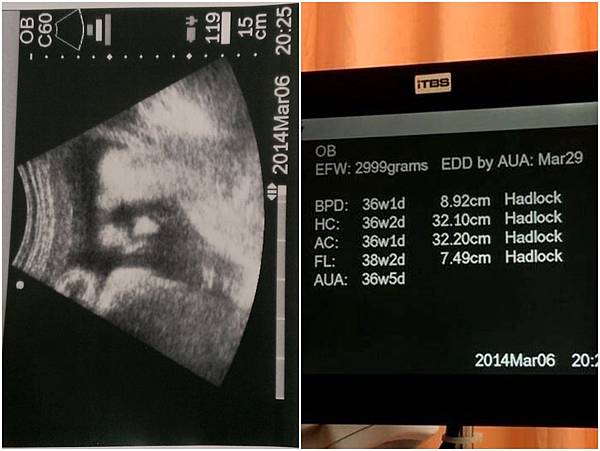

::37周產檢:: 義果體重2999G

這次產檢 義果乖乖的沒有再亂轉 乙型鏈球菌也順利過關

義果肉肉的臉 醫生也開玩笑的說 [看得出來寶寶的臉頰肉肉的 很可愛喔 養得很好喔]

聽到3000G時 我還是有點傻了@@

不過醫生說 寶寶的各個部位其實跟週數符合 只是腿比較長

我想......體重也是用各部位大小去推算的 只要頭不要太大 應該都還好生吧